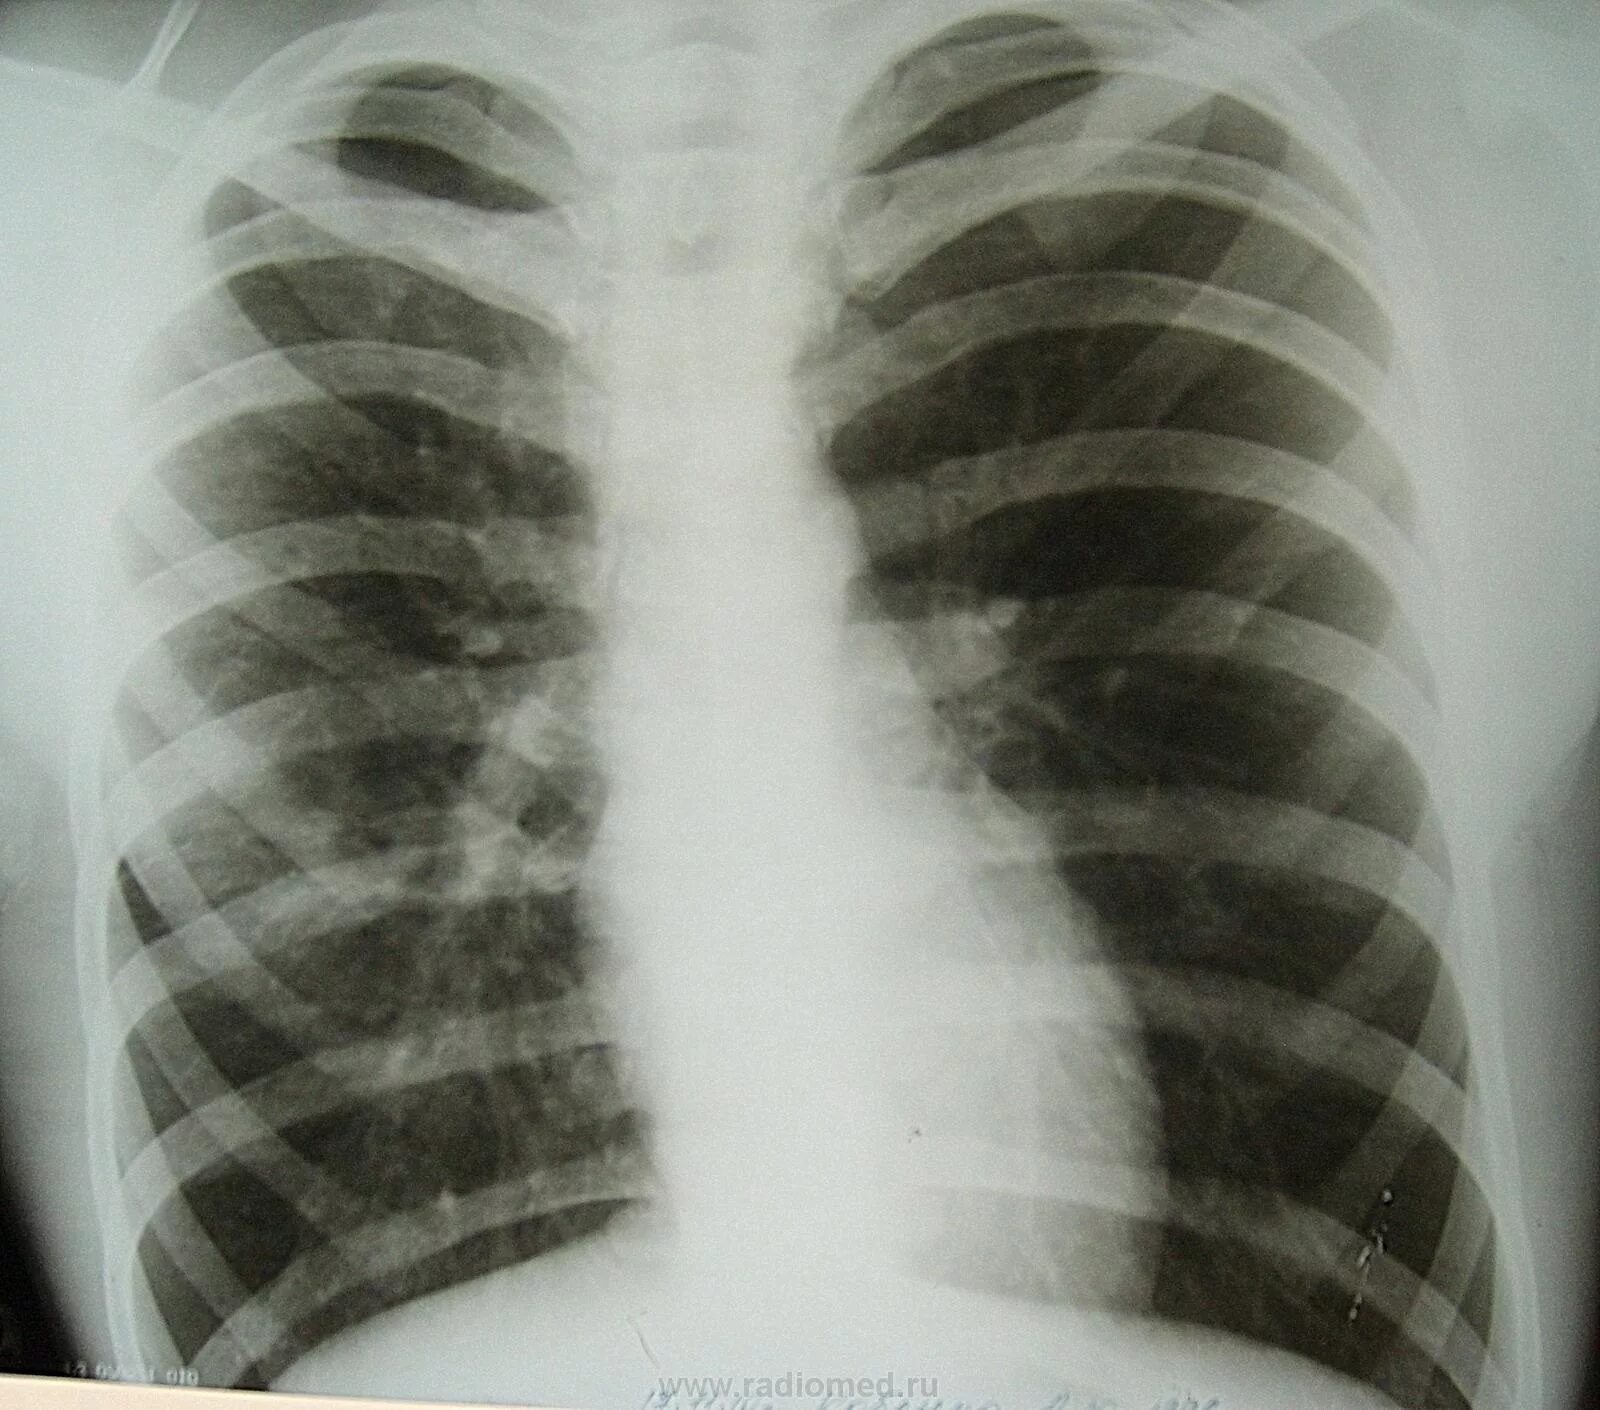

Пневмофиброзные изменения